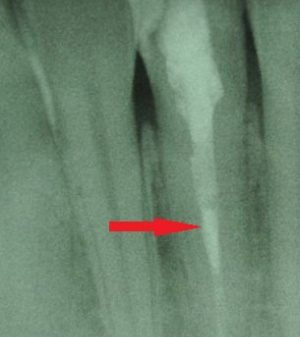

Dem Patienten wurden zunächst weiche Kost, eine Analgesie mittels Ibuprofen sowie eine Sportschutzschiene empfohlen. Die angesetzten Recall-Termine verliefen komplikationslos. Die letzte Kontrolle konnte fast drei Jahre später, am 07. März 2025, durchgeführt werden. Die Sensibilitätsprobe war positiv, der Perkussionstest unauffällig. Der Zahn war schmerz- und beschwerdefrei. Auch das angefertigte Röntgen in Form eines Zahnfilmes zeigt keine apikalen Aufhellungen, Resorptionen oder andere Auffälligkeiten.